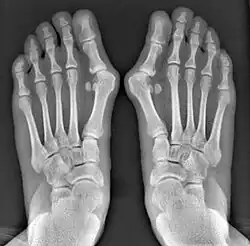

- For severe bunion deformity correction (Fig. 7)

- For recurrence correction after osteotomy procedure (Fig. 8)

Late deformity recurrence can happen after osteotomy (bone-breaking) procedures because osteotomy surgeries do not specifically stabilize first metatarsal bone.